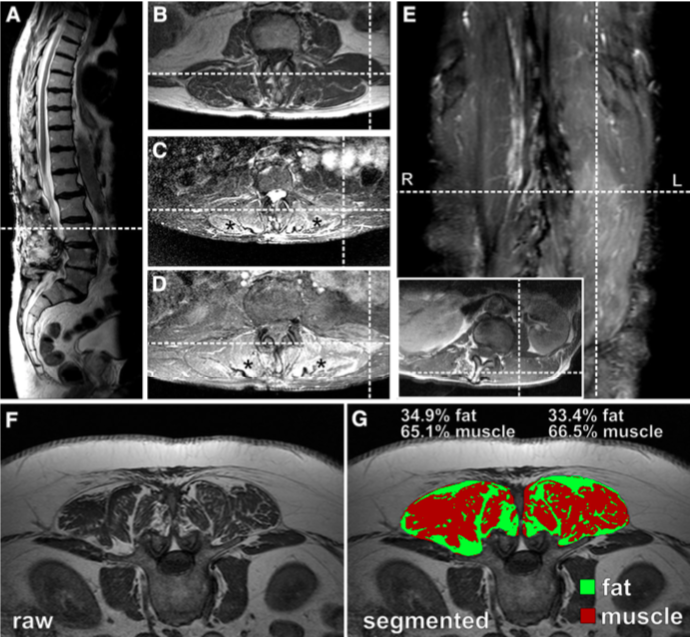

Margraf 等对伴躯干前屈症的帕金森病患者的脊柱肌肉进行MRI扫描,发现躯干前屈症肌肉水肿和脂肪浸润要较不合并躯干前屈症的帕金森患者更重,同时,水肿与脂肪变性与躯干前屈证的程度有关,与帕金森病的病程无关。